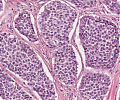

A92 Follikuläres Adenom der Schilddrüse

Randlicher Anteil mit mikrfollikulärem Aufbau (hohe Vergrößerung)

A92 Follikuläres Adenom der Schilddrüse

Randlicher Anteil mit mikrfollikulärem Aufbau (geringe Vergrößerung)

Follikuläres_Adenom1_SD_A92.png

Neoplastische Follikel unterschiedlicher Größe von isomorphen Follikelepithelien mit sog. Resorptionsvakuolen begrenzt

Follikuläres_Adenom_SD_A92.png

Follikulär gebaute Neoplasie mit gemischt mikro und normo-follikulärem Aufbau, umgeben von einer bindegewebigen Pseudokapsel.